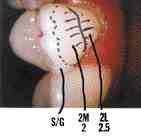

ABSTRACT: In 1994, the Dental Clinic was created at the Queensway Carleton Hospital (QCH), through the generous donation of Dr. M Lorne E. Macalchlan , a long-term care patient. The fund was earmarked for use in regards to elderly patients at the institution. The hospital itself is a 201-bed facility located in Nepean, Ontario, Canada … Read more